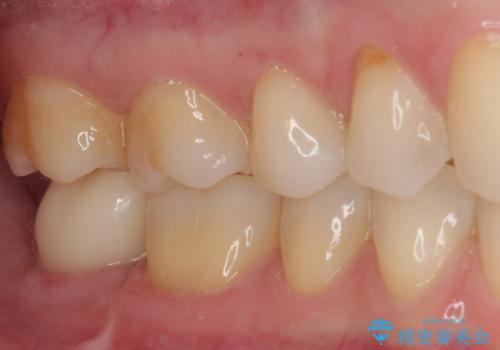

抜歯になった奥歯 速やかな埋入による短期間インプラント治療

- 奥歯が抜歯となり、インプラント治療を希望して来院された患者様です。

来院時には抜歯して1ヶ月ほど経過していたとのことで、3次元レントゲンよりインプラントの早期埋入が可能と診断されました。

インプラント埋入と同時に仮歯を装着するために、事前に仮歯を用意し、速やかにインプラント埋入を行うこととしました。